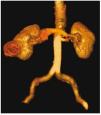

Figura 3. Vista posterior en reconstrucción 3D.